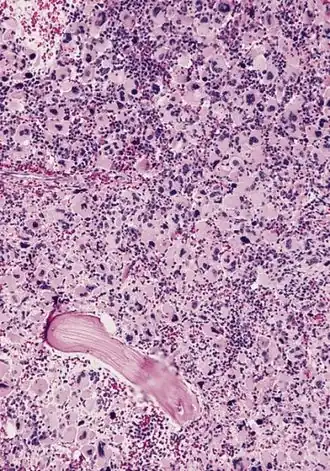

Description de cette image, également commentée ci-après

LAMK au myélogramme